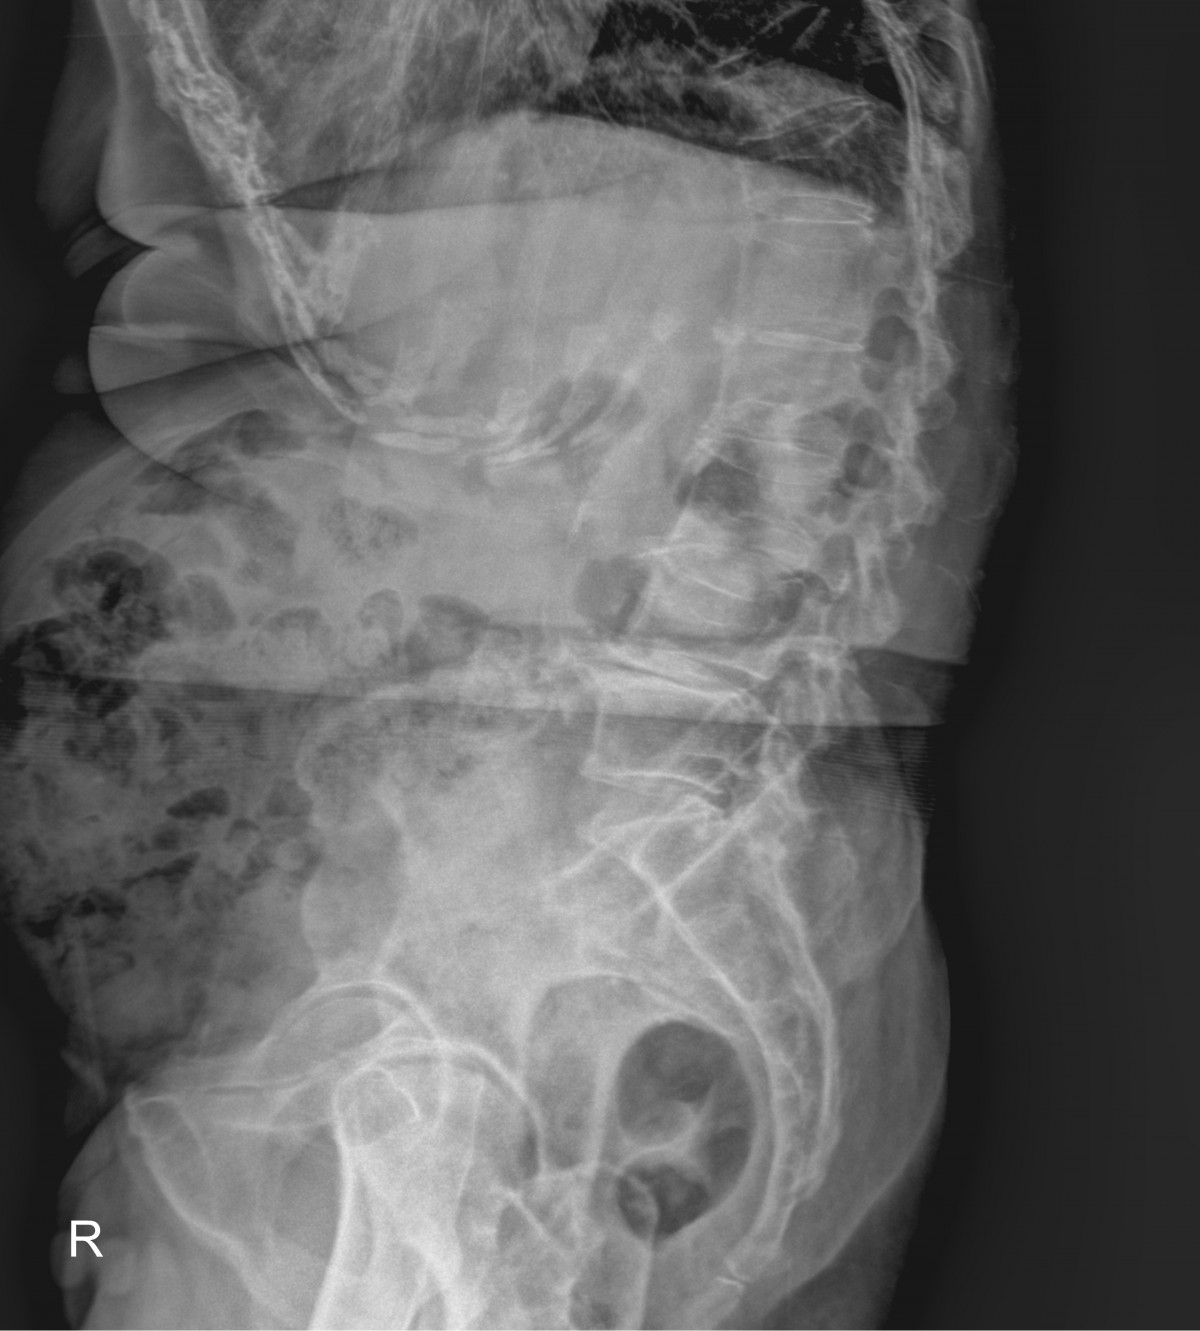

정지영원장님 흉추 골절 골시멘트 성형술 김월O 환자

작성자 최고관리자 댓글 0건 조회 688회 작성일 25-09-16 16:31

dae765e4d9ac96aee867c9d6292d8784_1758007890_9048.jpg